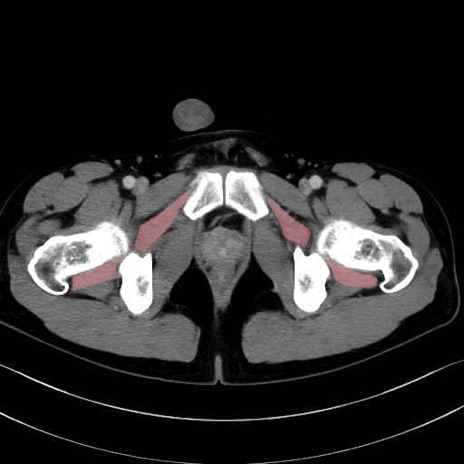

外閉鎖筋 (Obturator externus)